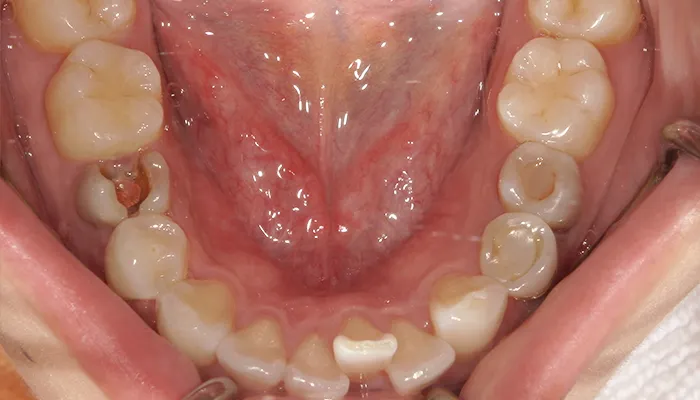

治療前

口腔内写真とレントゲン写真

右下5番は大きく崩壊しており、保存不可能な状態でした。

また、下顎前歯部を中心に叢生があり、歯列が不均一でした。咬合関係が不安定で、清掃性も低下していました。

全体的に歯の色もやや黄みを帯びており、患者様からも審美的な改善希望が強くありました。